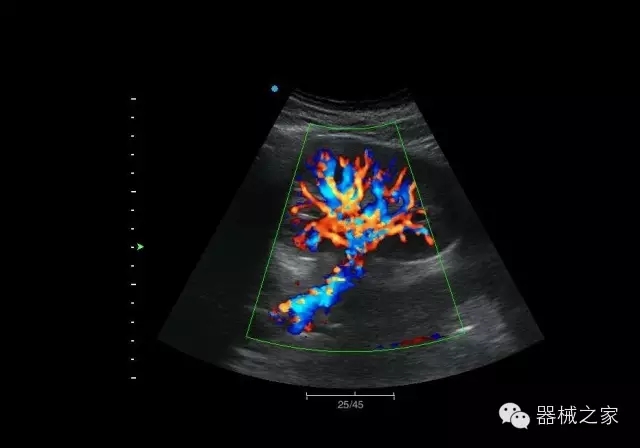

臨床圖片賞析

臍帶血流